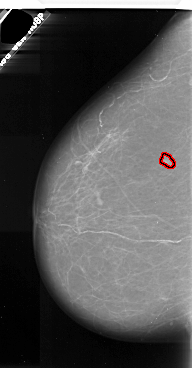

A_1073_1.LEFT_MLO

FILE: A_1073_1.LEFT_MLO.OVERLAY

TOTAL_ABNORMALITIES 1

ABNORMALITY 1

LESION_TYPE CALCIFICATION TYPE PLEOMORPHIC DISTRIBUTION CLUSTERED

LESION_TYPE MASS SHAPE IRREGULAR MARGINS ILL_DEFINED

ASSESSMENT 4

SUBTLETY 3

PATHOLOGY MALIGNANT

TOTAL_OUTLINES 1

BOUNDARY